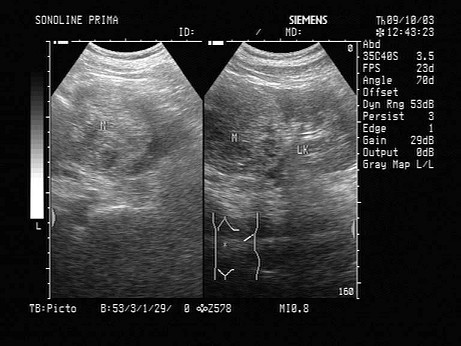

腰眼图片

腰窝图片,

腰眼深图片,

找腰眼的图片,

- 1.,60岁,无痛性血尿,腰部疼痛,该病例最可能的诊断 ( )